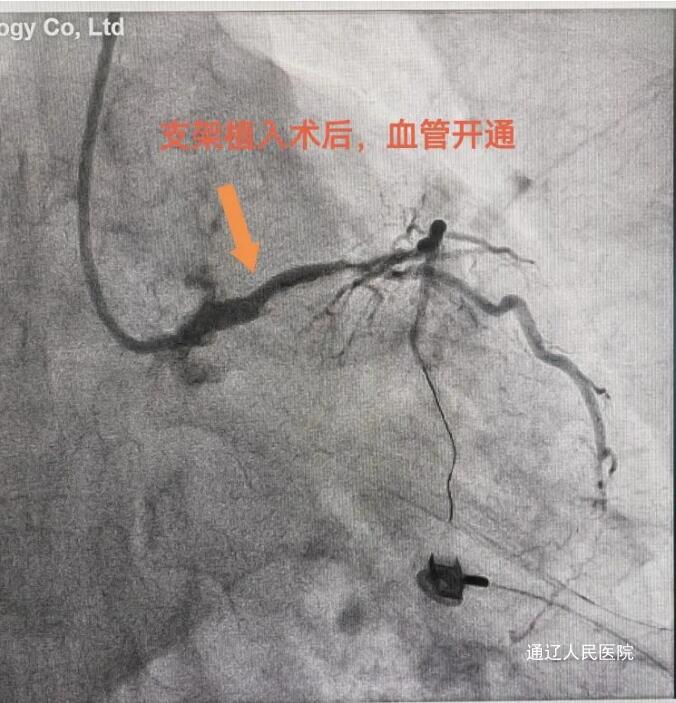

节假日期间,心内科的急诊手术并没有因节日来临而减少,大家依然忙碌着。近日,我院心内一科成功抢救一名65岁急性心梗患者,及时挽救了患者生命,有效提高了我院急性心梗患者的抢救成功率。患者阵发性胸痛持续10天,每次2-3分钟,未在意,6月9日突然加重,持续不缓解,急来我院就诊。行心电图检查提示广泛导联ST段下移,avR导联ST段抬高,接诊的心内一科李颖医生结合患者症状及心电图检查考虑左主干病变,病情危重,迅速启动导管室。紧急通知导管室医护人员做好术前准备工作;积极与患者家属沟通,详细解释病情的危险性及解决方案,征得患者及家属的同意后,迅速将患者送入导管室。患者冠脉造影如预测所示,左主干99%狭窄伴血栓形成,前降支、右冠均有程度不同的狭窄、重度钙化,回旋支从开口处即闭塞,为慢性闭塞。通常左主干+三支病变首选外科冠脉搭桥治疗,但本患者急性发病,持续胸痛,且左主干几近闭塞,死亡风险极高。对于这样的危急情况来说时间就是生命,尽早开通梗阻的血管,使心肌得到血液再灌注,是救治的关键。手术由吴哲主任医师和律桃园副主任医师进行,术前做好预案、充分准备,手术全程由导管室护士周文明、贾菲菲、陈瑜全力配合保驾护航,最终在大家的共同努力下,患者得到成功救治收入CCU进一步治疗。

冠状动脉左主干急性闭塞所致急性心肌梗死尤为凶险,大多迅速发展成心源性休克或死亡,有些患者发病不能及时到达医院,多表现为猝死,或者成功存活者随访的严重不良事件发生率仍较高。本例患者左主干99%狭窄,几近闭塞,命悬一线,在医护人员的共同努力下,通过介入治疗为患者争取到了一线生机。我院现已常规开展冠脉慢性闭塞病变、左主干病变、分叉病变、急诊介入等高难度心血管介入手术。今后,通辽市人民医院将持续依托强大的技术实力和专家团队优势,为患者带去更便捷、优质的医疗服务,为患者生命保驾护航。